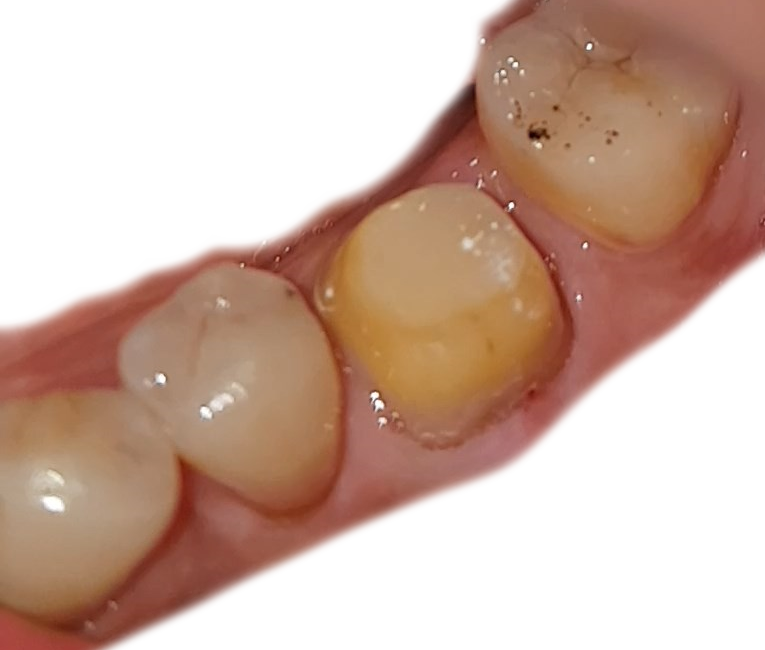

크라운을 씌울 이빨에 청소 및 소독을...진행한다.

저 이빨에 검은 찌거지들은..무엇인지 모르겠으나...

뭔 잉크 같은 것이라고...양치를 하면 없어진다고 한다..

사진에 계속 있어서...영...이빨이 보기흉하다.